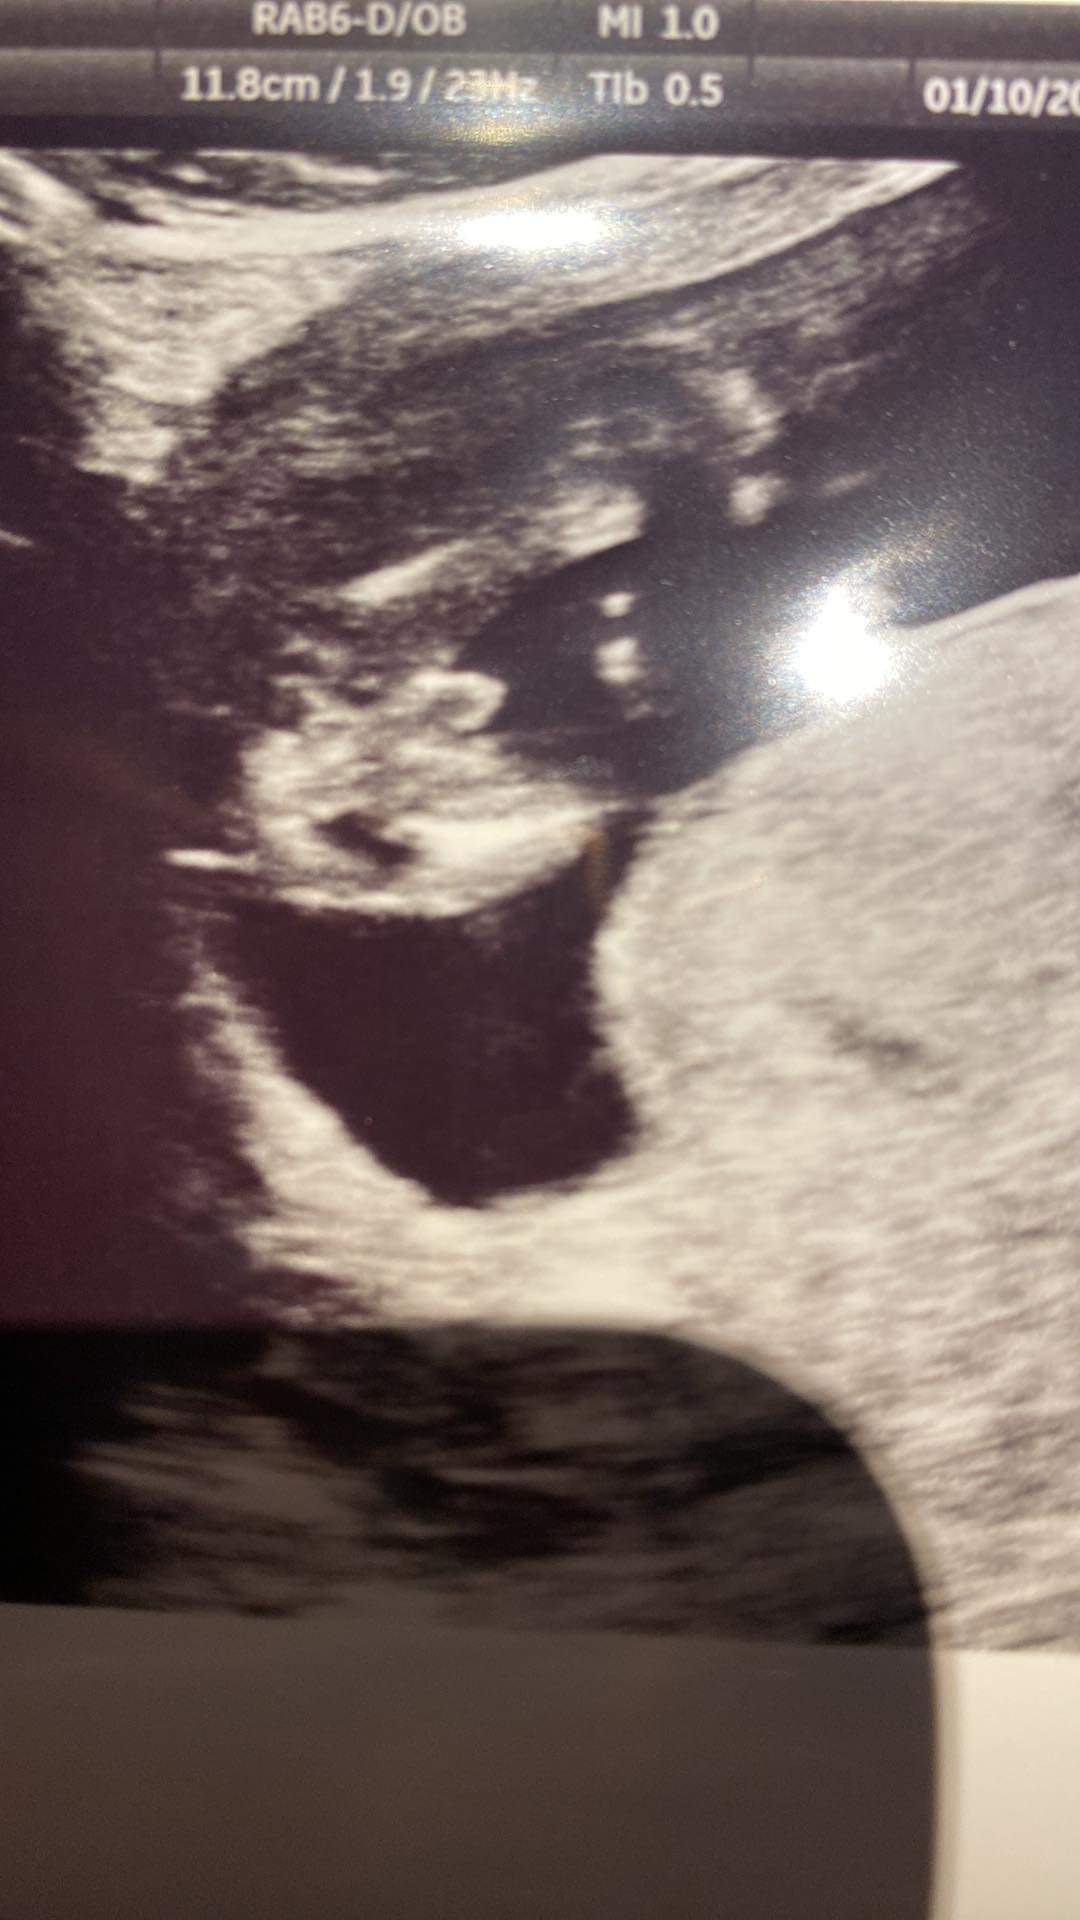

Dziewczyny pomóżcie :) chłopak czy dziewczynka? Lekarz mówi że raczej chłopak ale może być też dziewczynka bo często zdarza się przerośnięta łechtaczka. Jak Wy myślicie?

Ktory to tydzień? A lekarz coś mówił?:)

Powiedział że pewnie chłopak ale nie wyklucza dziewczynki bo noże to też być przerośnięta łechtaczka ponoć tak się często zdarza a wtedy te narządy wyglądają podobnie jeszcze w tym czasie. Tak powiedział w 14 tc a pózniej to samo prowadząca moja powiedziała w 15 tc